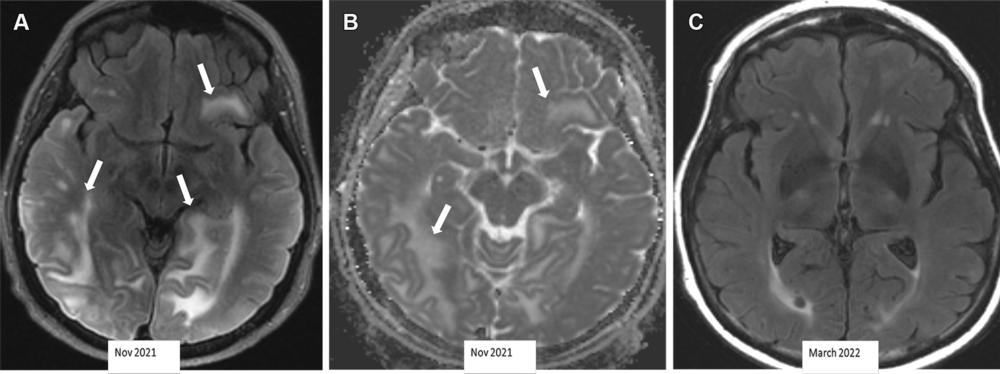

Figure 7. Severe ARIA-E (edema) in a 69-year-old woman receiving aducanumab therapy for AD with headaches and word-finding difficulty. (A, B) Axial MR images of the brain show multifocal subcortical edema (arrows) with FLAIR hyperintensity (A) and increased diffusion on the apparent diffusion coefficient (ADC) map (B), with a few areas measuring more than 10 cm. (C) Axial follow-up MR image 4 months later shows near-complete resolution of signal intensity changes. ARIA-E is most common in the occipital lobes (as in this case) and mimics posterior reversible encephalopathy syndrome (PRES) at imaging.

High-res (TIF) version